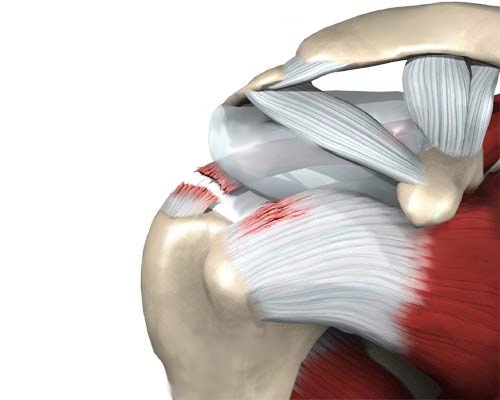

Разрыв сухожилия надостной мышцы часто происходит из-за падений на выпрямленные руки или ударов по плечу. Долгосрочное применение гормональных препаратов может ослабить связки, и даже незначительное воздействие в таких случаях может вызвать травму. Аналогичные последствия наблюдаются у курильщиков. Травмы возникают, как правило, из-за резких движений или чрезмерного отведения руки.

Мышцы и связки плечевого пояса содержат множество нервных окончаний и кровеносных сосудов. Это приводит к сильной боли, отечности и образованию гематом при разрыве или растяжении. Подвижность сустава значительно ограничивается, а при пальпации пораженной области боль усиливается. При легких травмах симптомы могут проявиться через несколько дней, в то время как в первые часы боль может быть незначительной.

Разрывы связок плеча классифицируются на три степени тяжести, в зависимости от количества поврежденных волокон:

- При легких травмах происходит частичное повреждение сухожилия, при этом нервные окончания и сосуды остаются неповрежденными. Гематомы и отеки не возникают, а болевой синдром выражен умеренно. Восстановление при правильном лечении занимает не более двух недель.

- Разрывы второй степени затрагивают значительную часть связки и двуглавой мышцы плеча. В этом случае наблюдаются выраженная отечность, кровоизлияние в сустав, сильная боль и ограничение подвижности. Реабилитация занимает от одного до двух месяцев.

- Тяжелые травмы характеризуются полным разрывом сухожилия, мышцы и суставной сумки. Плечо становится патологически подвижным. Лечение может длиться более двух месяцев, а в сложных случаях может потребоваться хирургическое вмешательство.